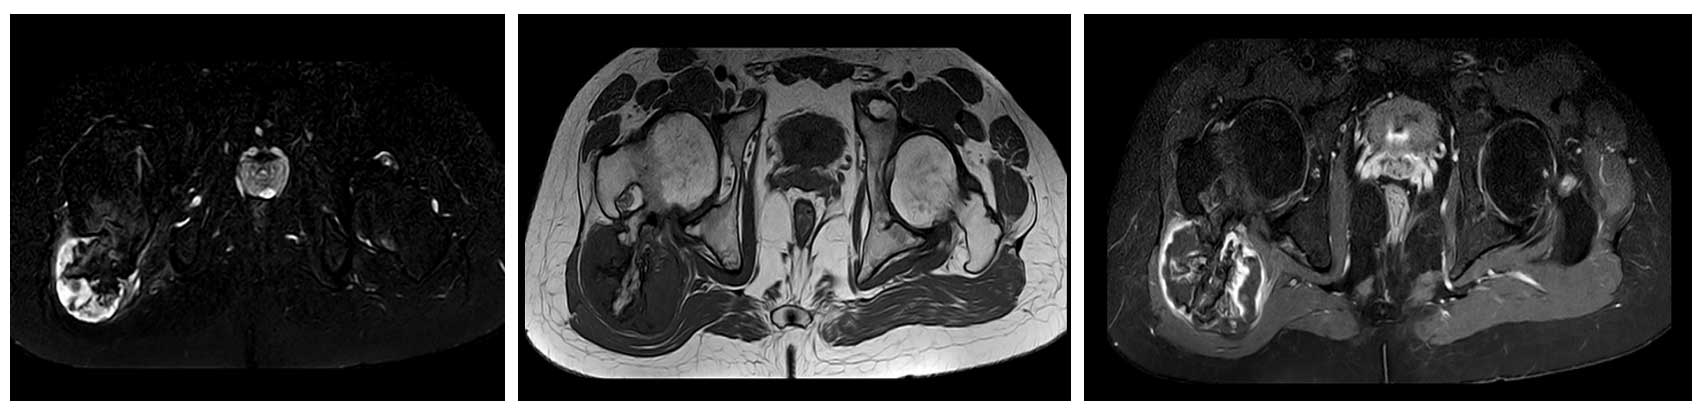

Ameliyat Öncesi: MR’da tümör çevresinde kıkırdak şapka ve ödem görülmekte.